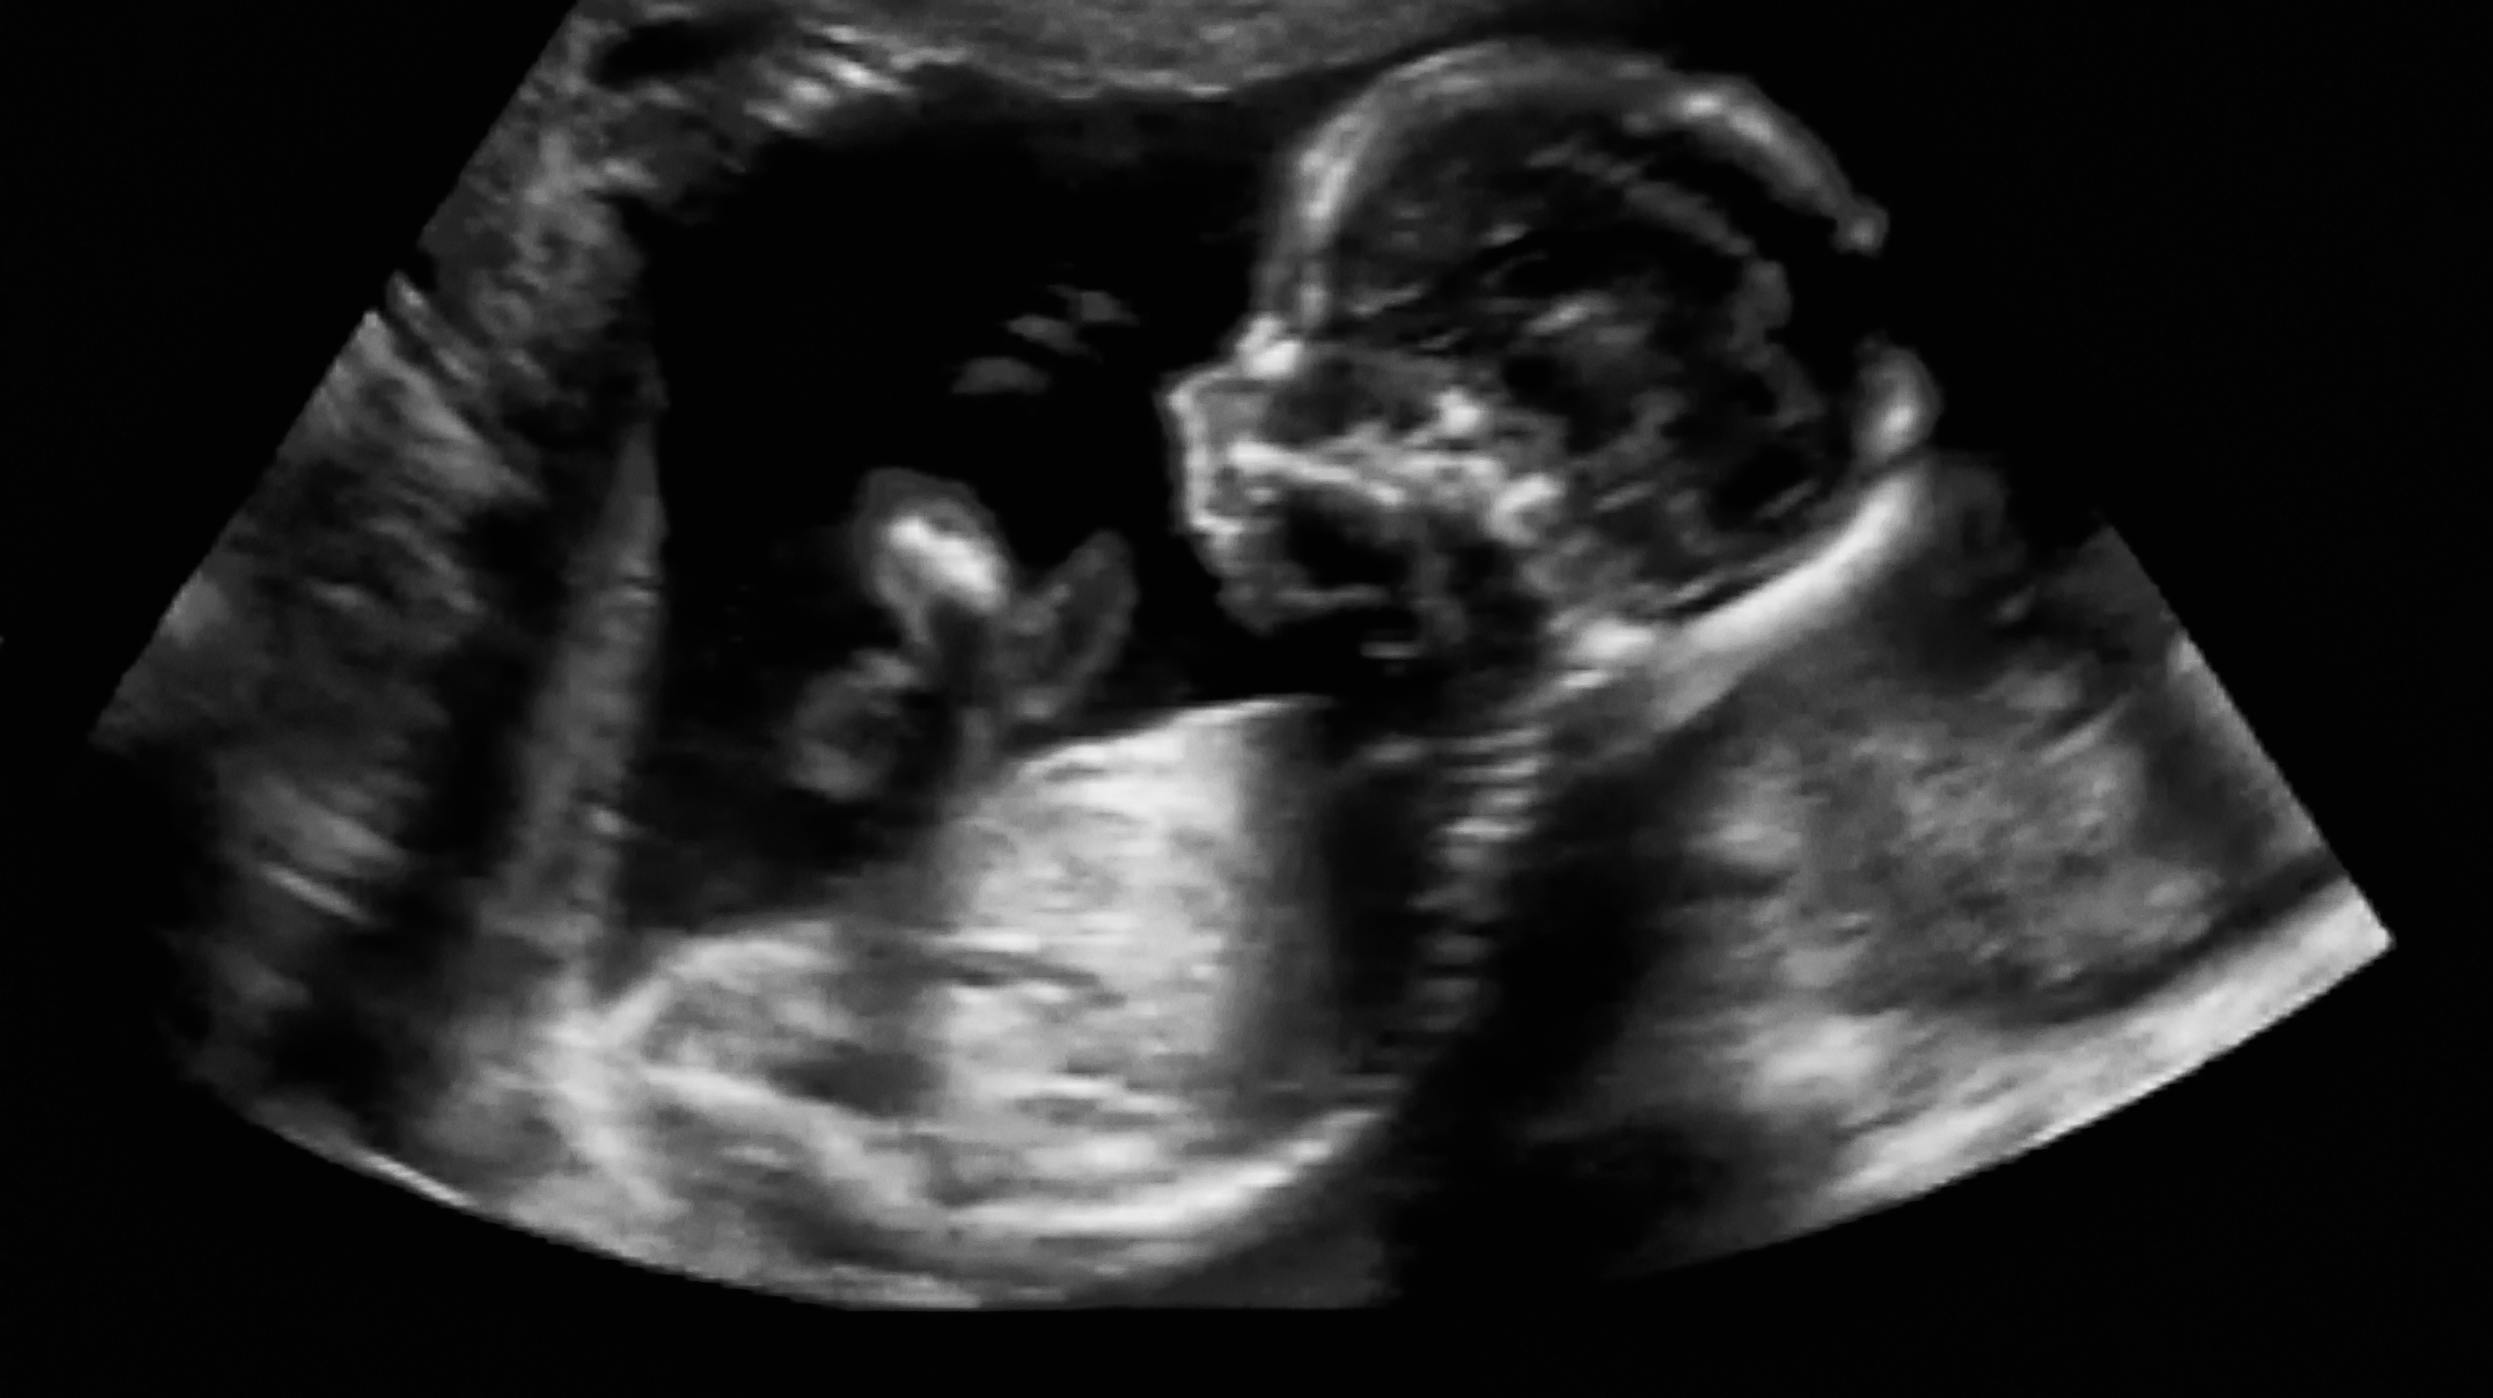

Den nuværende grænse på 12 uger giver nemlig ikke mening, fordi første scanning – den såkaldte nakkefoldsscanning - ligger i uge 12, og dermed får langt de fleste par først svaret efter abortgrænsen.